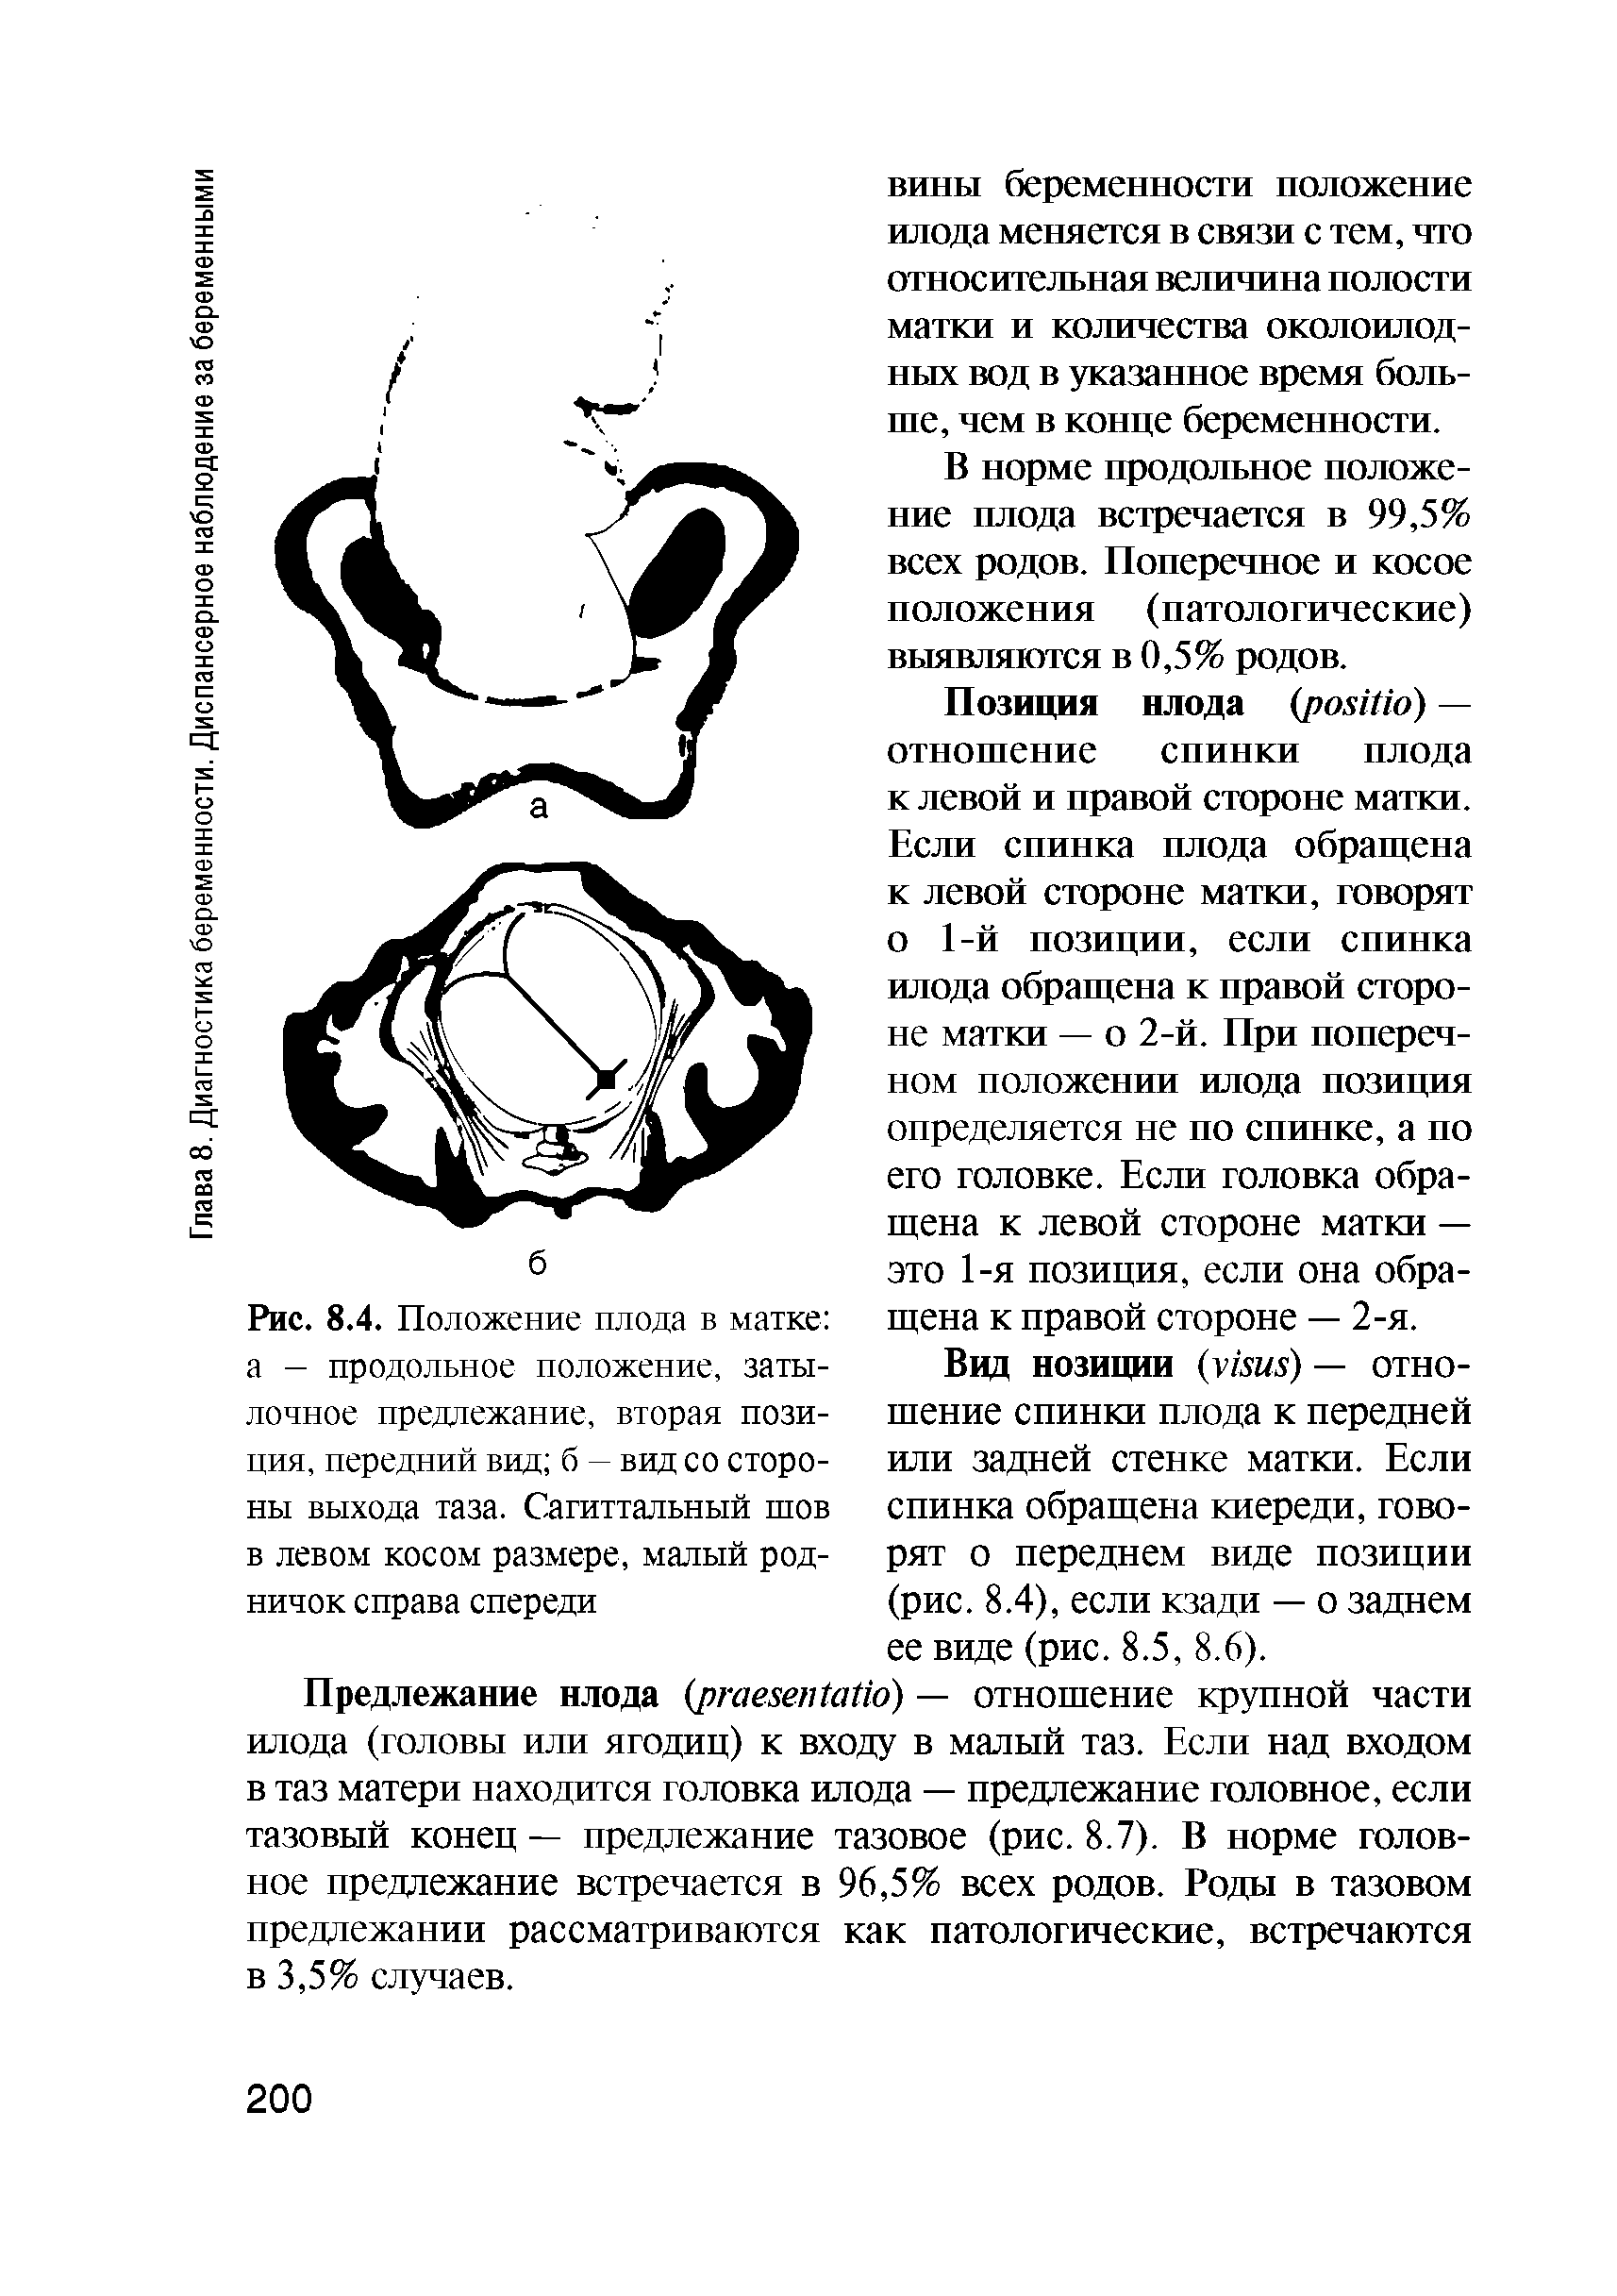

Во время беременности, положение плода имеет большое значение для мамы и малыша. Одним из типичных положений является продольное предлежание головное. В этом положении голова малыша находится внизу, а ножки - наверху. Это положение достаточно распространено и предпочтительно для естественных родов.

Фото положения плода во время беременности

Ниже приведены несколько фотографий, которые помогут вам визуализировать положение плода во время беременности.